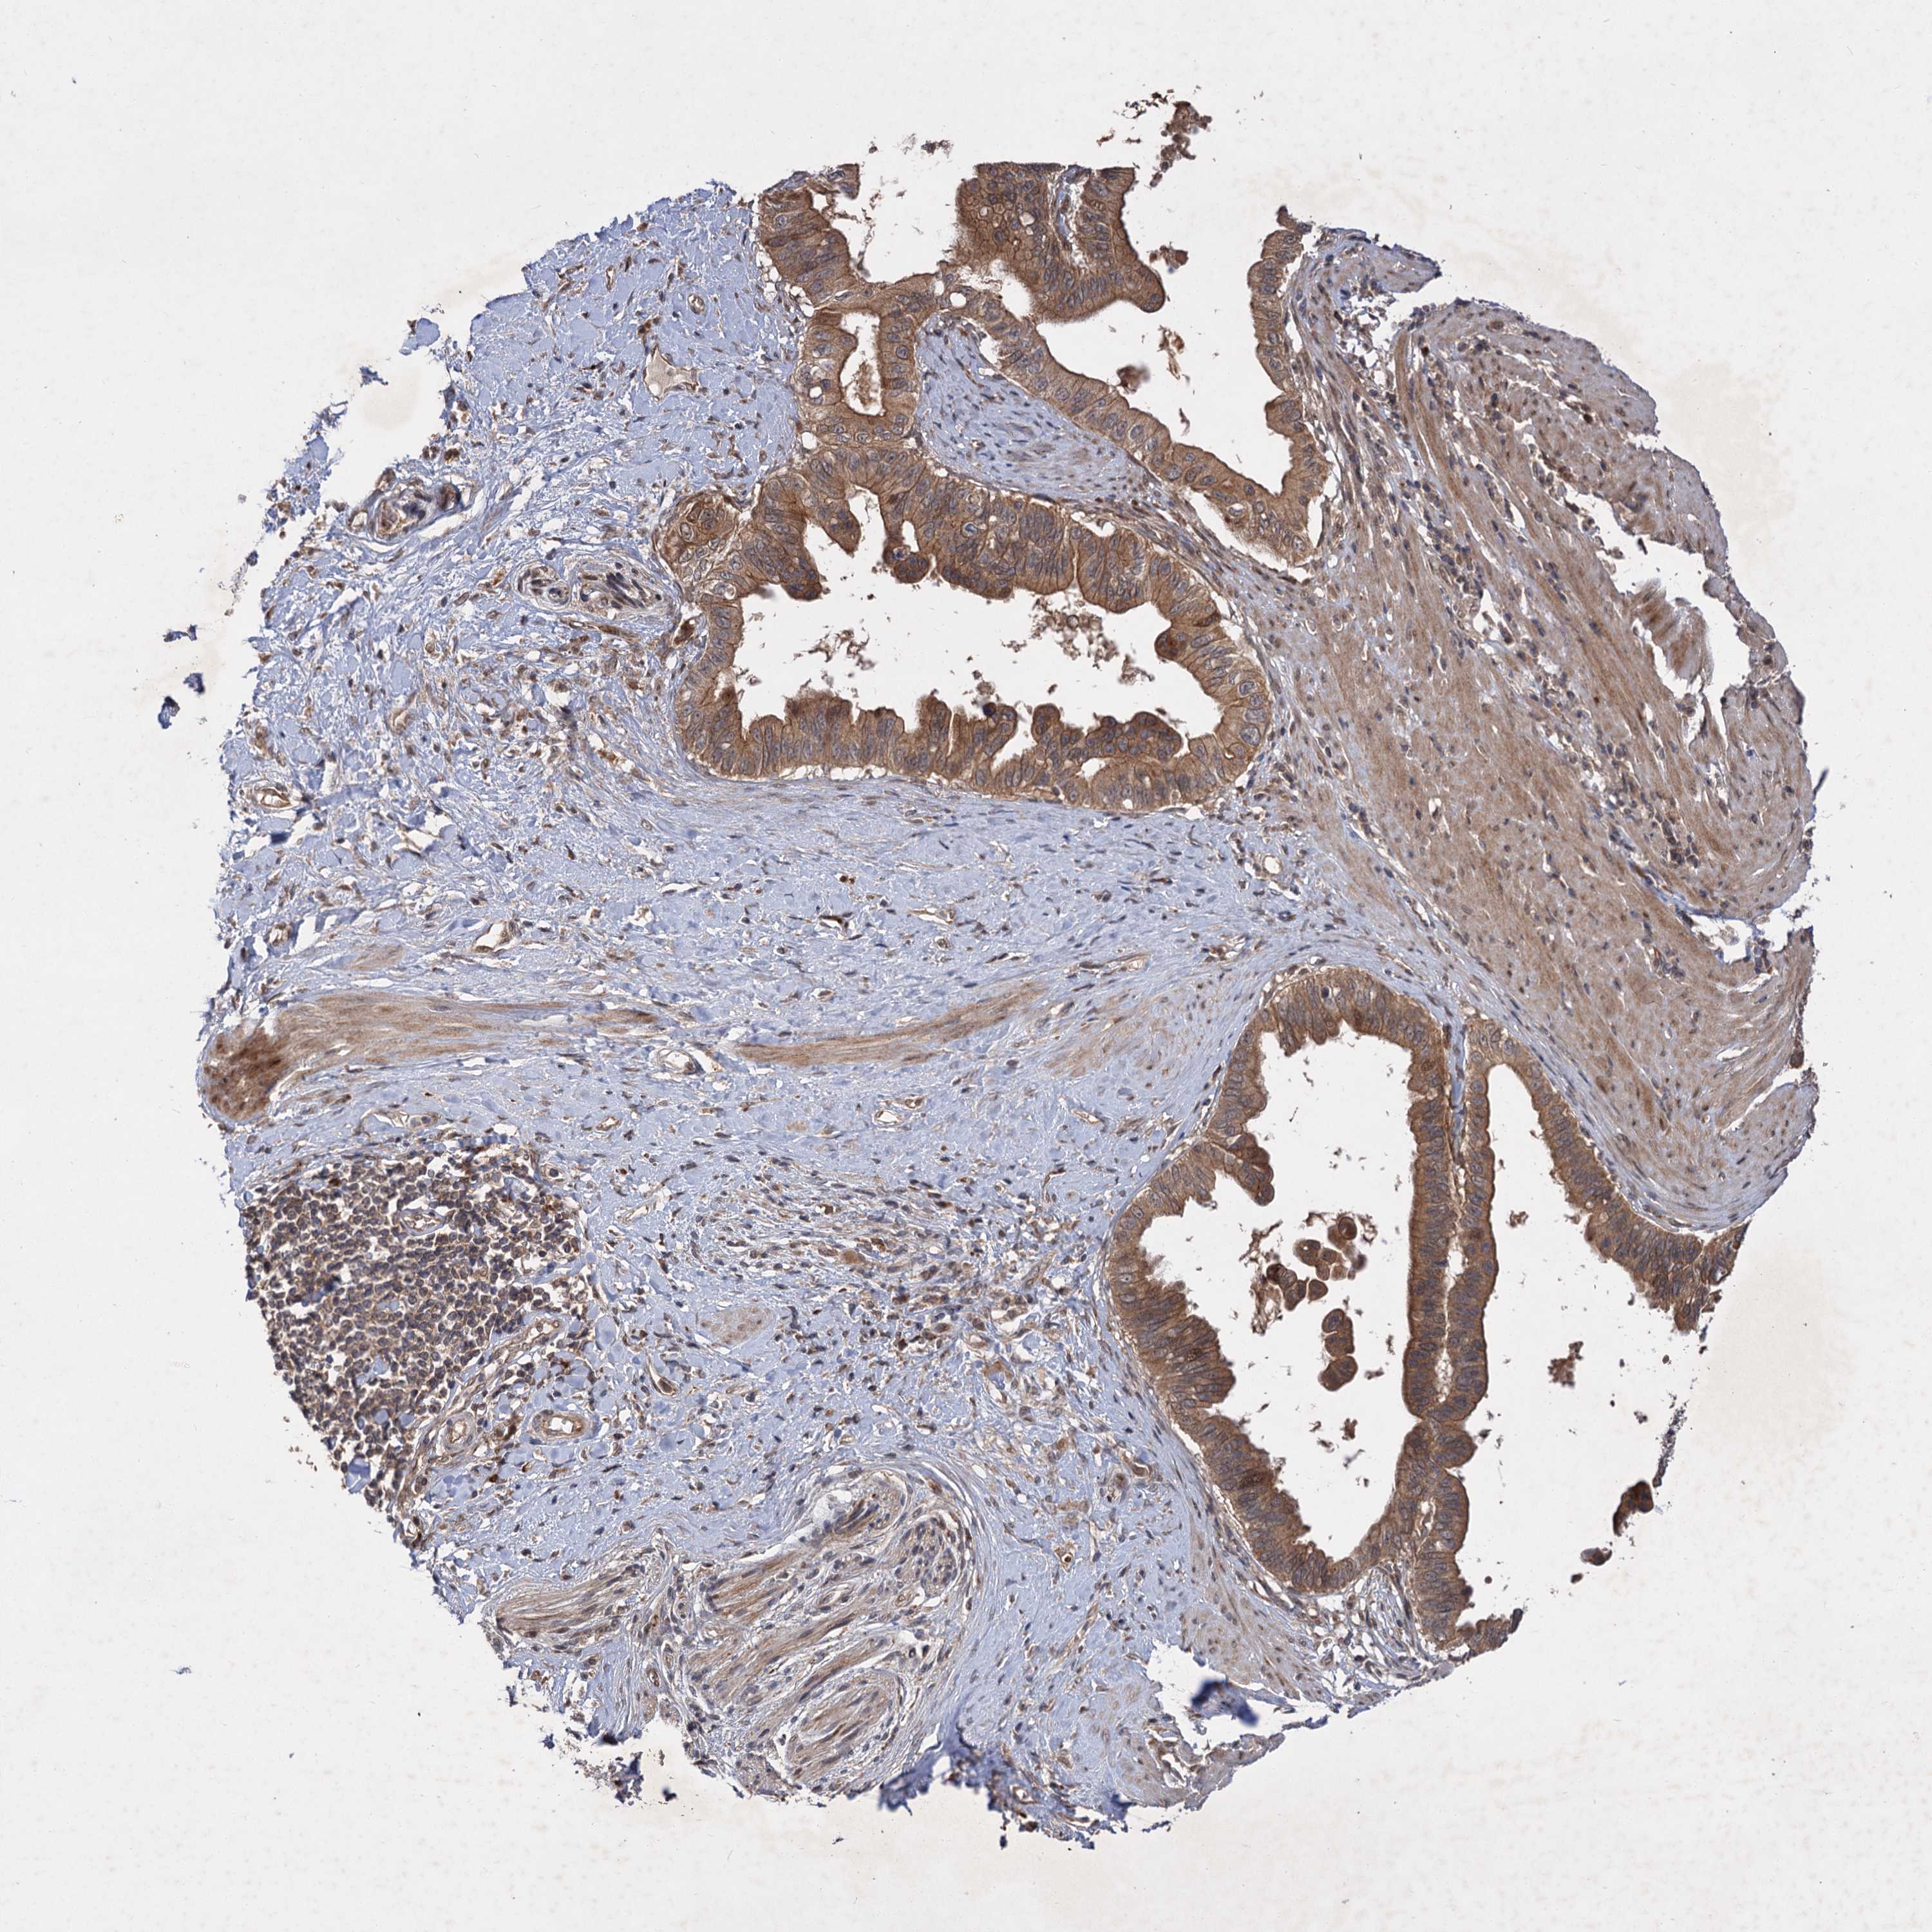

PANCREATIC CANCER - Protein expressioni

A mouse-over function shows sample information and annotation data. Click on an image to view it in a full screen mode. Samples can be filtered based on level of antibody staining by selecting one or several of the following categories: high, medium, low and not detected. The assay and annotation is described here.

Note that samples used for immunohistochemistry by the Human Protein Atlas do not correspond to samples in the TCGA dataset.

Antibody stainingi

Antibody staining in the annotated cell types in the current human tissue is reported as not detected, low, medium, or high, based on conventional immunohistochemistry profiling in selected tissues. This score is based on the combination of the staining intensity and fraction of stained cells.

Each image is clickable and will lead to virtual microscopy that enables deeper exploration of all samples and also displays staining intensity scores, fraction scores and subcellular localization as well as patient and tissue information for each sample.

Antibody HPA038850

Antibody HPA038851

Staining

High

Medium

Low

Not detected

Intensity

Strong

Moderate

Weak

Negative

Quantity

>75%

75%-25%

<25%

None

Location

Nuclear

Cytoplasmic/membranous

Cytoplasmic/membranous,nuclear

Adenocarcinoma, NOS